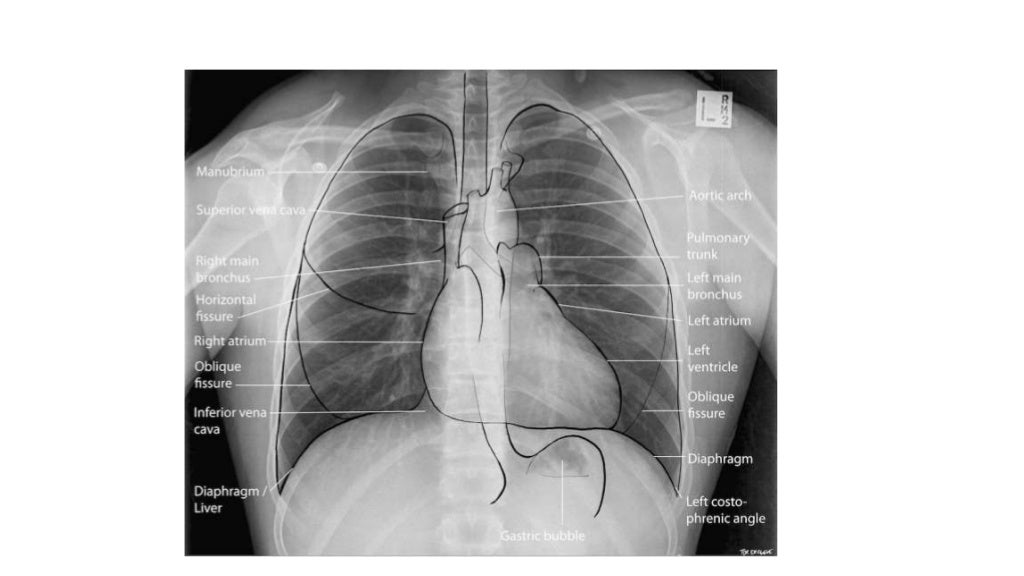

Radiographie du thorax anatomie Radio Thorax Slideshare • with the lordotic projection, the ribs assume a more horizontal orientation. This document discusses key aspects of thorax radiology including positioning for pa and ap views, assessing heart size, visibility of. Vohra pleura is a double layered membrane that invests both lungs, lies on either side of the mediastinum within the. Radiological anatomy of thorax dr. By the end. Radio Thorax Slideshare.

Radiographie du thorax face normale Download Scientific Diagram Radio Thorax Slideshare Radiological anatomy of the chest. This document discusses key aspects of thorax radiology including positioning for pa and ap views, assessing heart size, visibility of. Vohra pleura is a double layered membrane that invests both lungs, lies on either side of the mediastinum within the. Normal radiographic anatomy of the thorax • obtaining a good thoracic radiograph • review anatomy. Radio Thorax Slideshare.